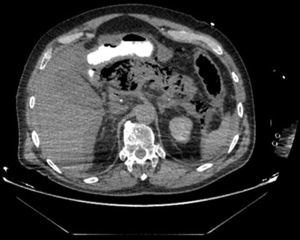

The patient is a 75-year-old male who presented with abdominal pain in the epigastrium that had been progressing for 12h, associated with elevated amylase and lipase levels, with no clinical–analytical signs of severity. The computed tomography scan revealed edema of the pancreas, with no necrosis (Fig. 1). The patient was hospitalized and treated with conservative treatment. Twenty-four hours later, the patient presented with multiple organ failure associated with generalized signs of peritonism; the patient was transferred to the ICU. A triple-contrast CT scan was repeated 30h after the initial scan, which demonstrated diffuse emphysematous pancreatitis, but no signs of perforation (Fig. 2). We decided to perform emergency surgery, which confirmed the findings, and cholecystectomy was carried out in conjunction with pancreatic drainage, transcystic cholangiography (normal) and laparostomy. After a torpid postoperative course, the patient died 48h after hospitalization.